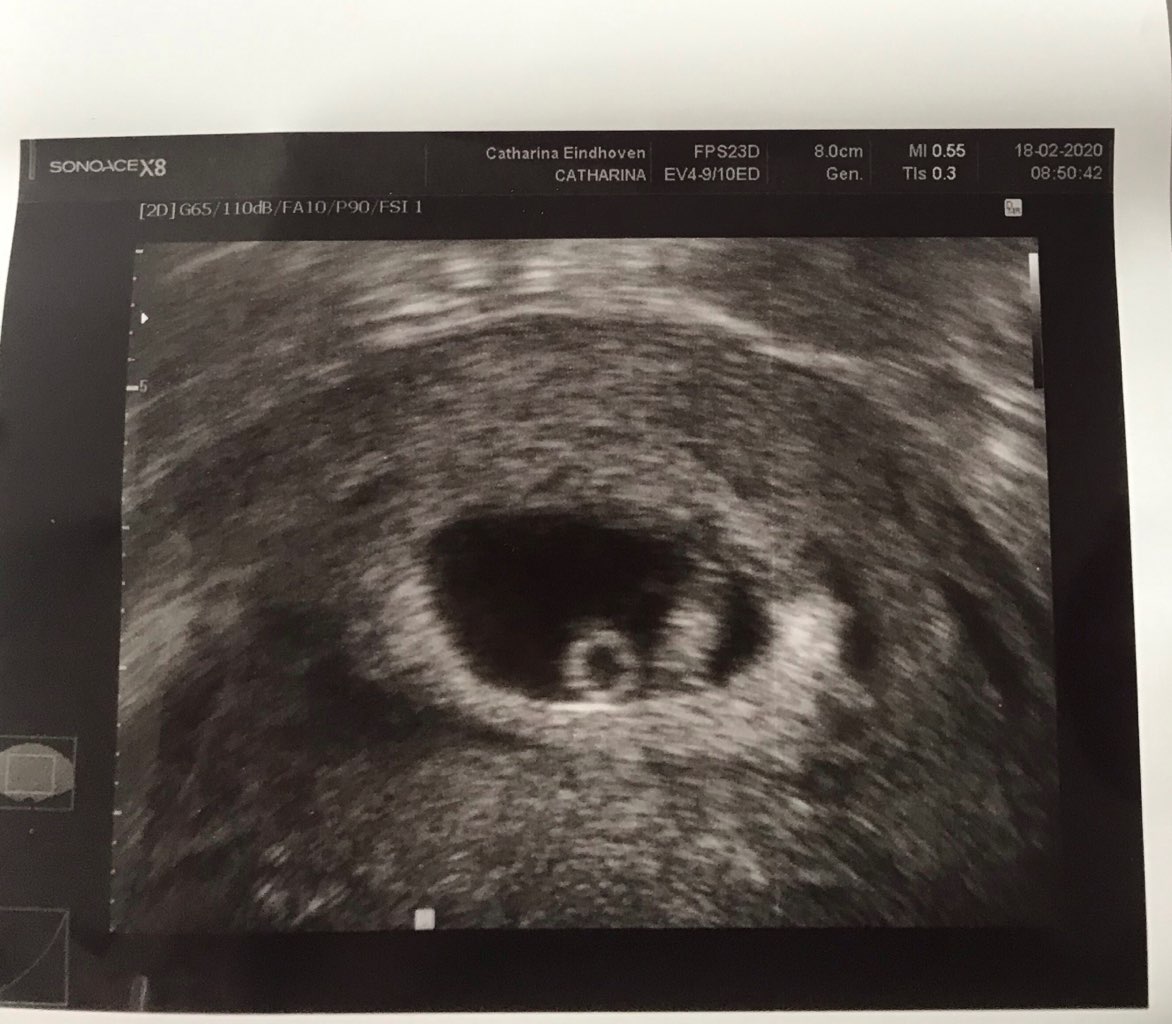

mój nie był jakiś bardzo spłaszczony ale tez była taka kropelka, zdjęcie pierwsze te płaskie z 26dpt, a drugie z 33dpt(dopiero tu było serce)

No u Ciebie lepiej to wyglądało :) ale dzięki może u mnie też się to jakoś zmieni jeszcze. Ja dziś 23 dpt i było serduszko. Nie spodziewałam się tego.